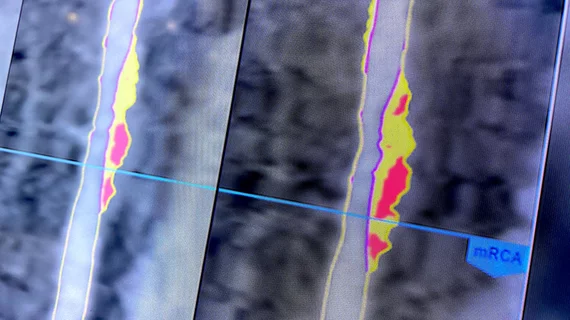

TEROBOSAN BARU! Dokter Kini Bisa Deteksi Plak Berbahaya di Pembuluh Darah Menggunakan Cahaya – Teknologi NIRS untuk Identifikasi Plak Rentan

Dalam beberapa tahun terakhir, dunia kardiologi mengalami perkembangan pesat, terutama dalam teknologi pencitraan intrakoroner yang membantu dokter memahami kondisi pembuluh […]